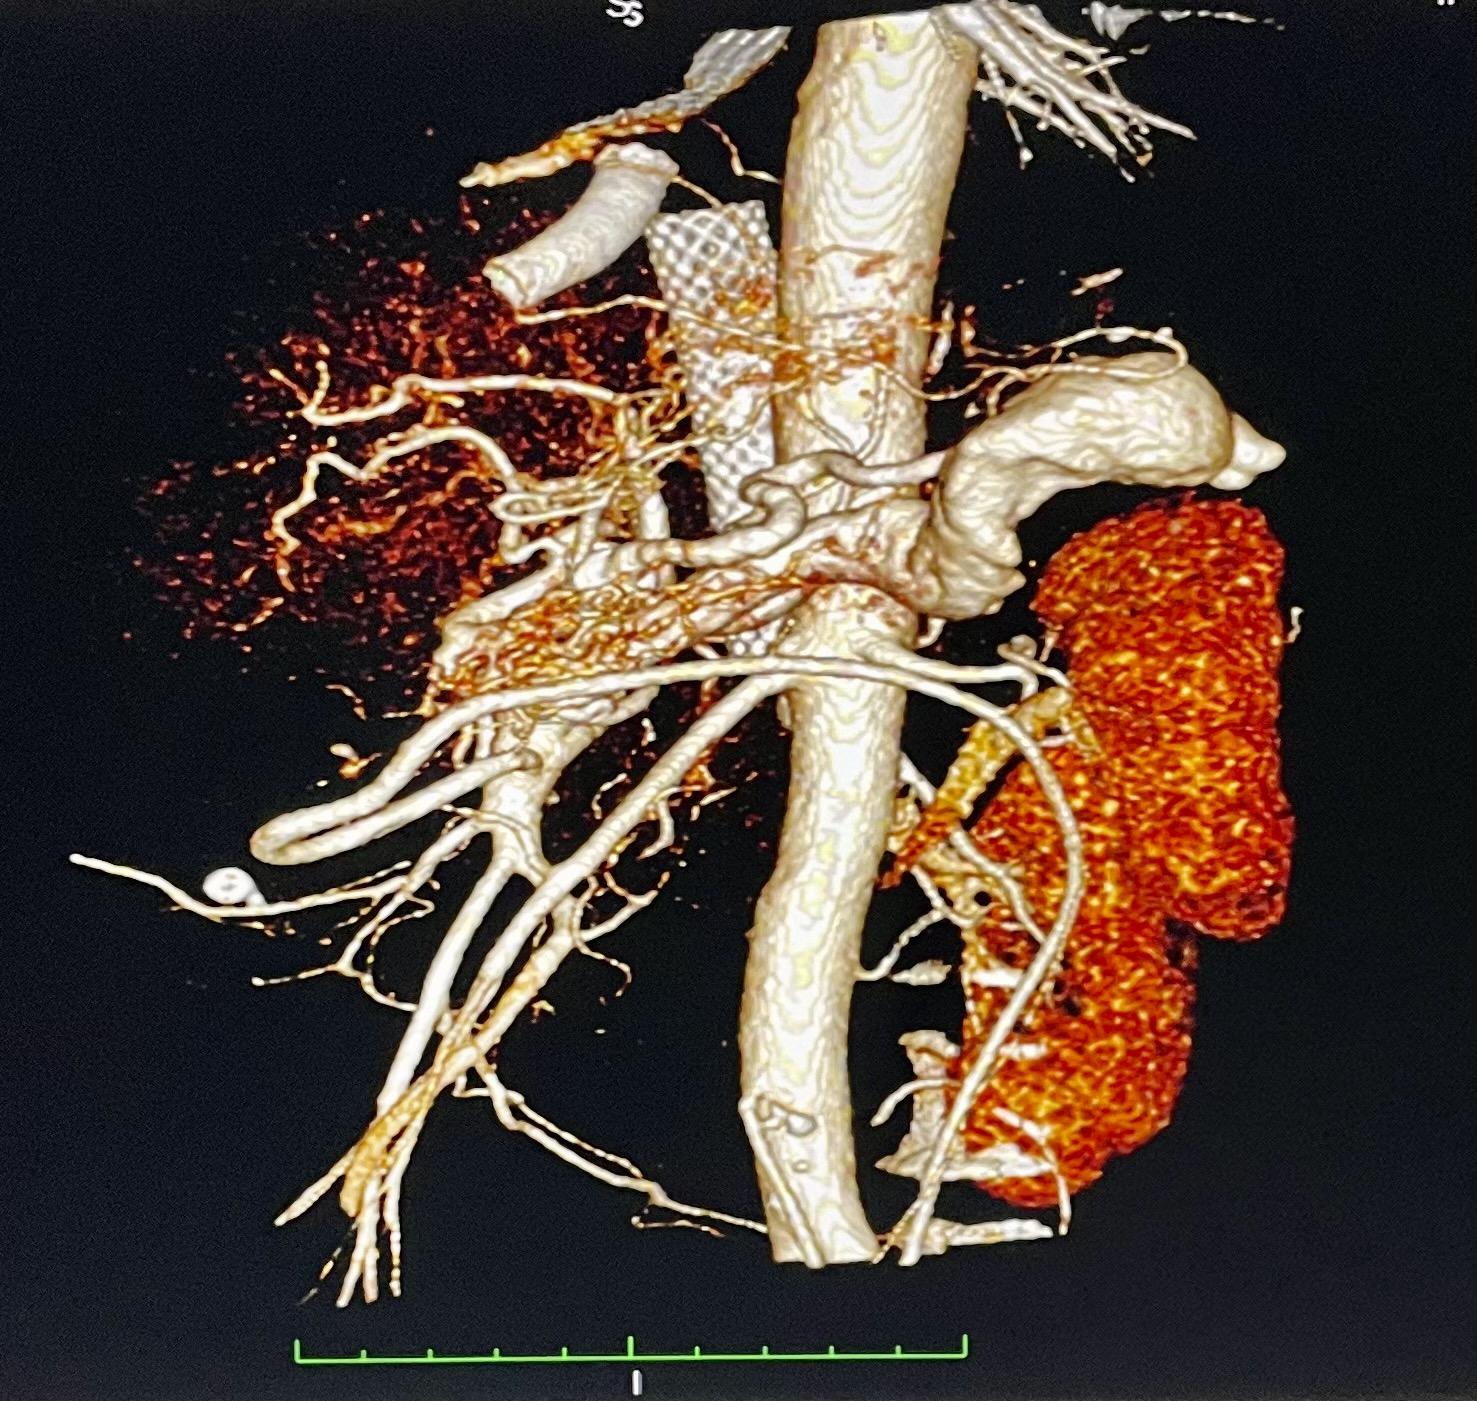

1. КТ-ангиография с 3D-реконструкцией сосудов | |